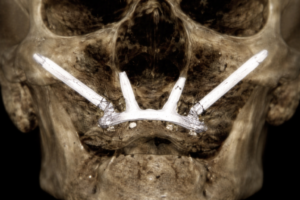

Implantes Cigomáticos

Implantes de anclaje al hueso cigomático indicados en pacientes con reabsorción ósea severa del maxilar superior. Ofrecen una solución fija y predecible sin necesidad de injertos óseos complejos.